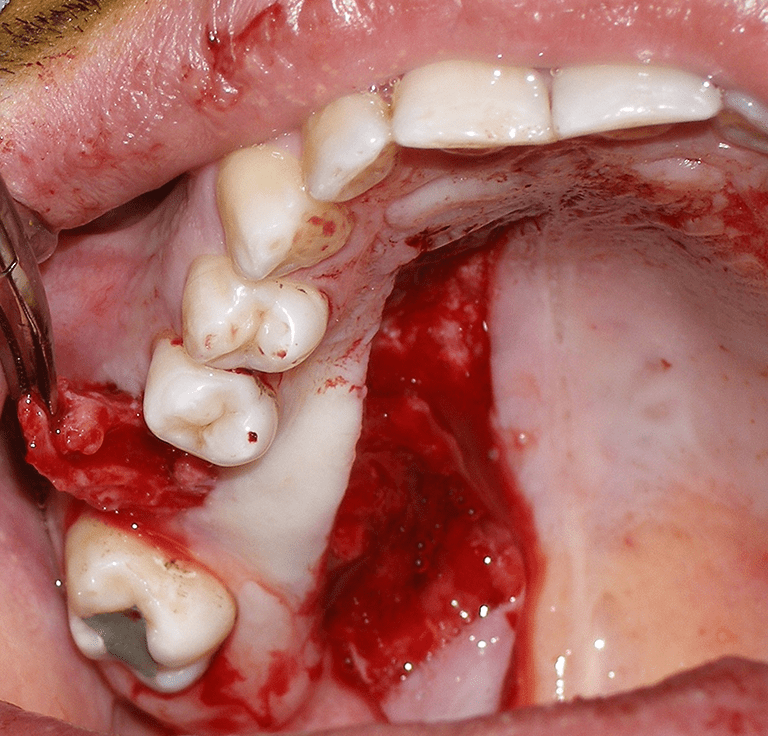

This case – a 30-year-old man visited the emergency department with a history of 4 months of purulent nasal discharge and facial pain in the context of upper left molar extraction that did not respond to long-term antibiotic treatment. Nasal endoscopy showed purulent discharge coming from the left middle meatus and a bulging uncinate process. Oral cavity inspection manifested granulation tissue with purulent discharge at the site of tooth 26. Facial and paranasal sinuses computed tomography (CT) was performed, it showed an 11 mm bone defect at the left maxillary floor concerning tooth 26 and a complete opacification of the maxillary sinus with osteomeatal complex obstruction